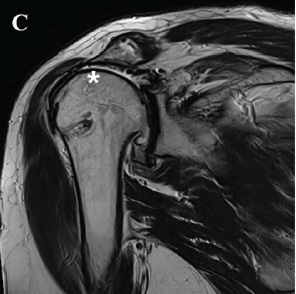

Arthroscopy-Assisted Lower Trapezius Tendon Transfer Combined with Superior Capsular Reconstruction in Posterosuperior Irreparable Rotator Cuff Tears: A Case Report

Chang Hee Baek , Chaemoon Lim , Jung Gon Kim , Bo Taek Kim

………………………………p.183-189